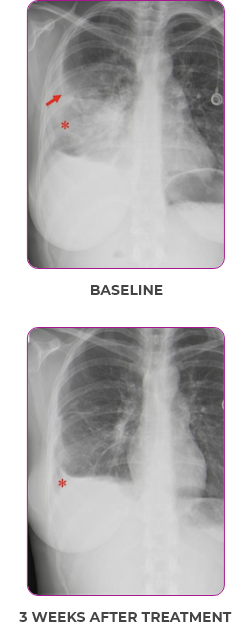

PATIENT CASE:

METASTATIC NSCLC1,a

- PRa after 6 weeks of treatment with VITRAKVI® (larotrectinib)

- Complete clinical response achieved by 12 months with residual scarring

Response to VITRAKVI1

- Partial response and symptom improvement confirmed by chest X-rays after <1 month of treatment

- Imaging performed 6 weeks into treatment revealed considerable decrease in the size of both target lesions

Response in primary and metastatic lesions1

Lung imaging of primary tumors.

SCAN 1: LUNG

SCAN 2: LUNG AND BONE

Images courtesy of Dr Maximilian Hochmair.